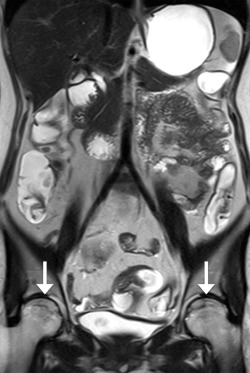

No definite inflammatory spondyloarthropathy (such as sacroiliitis) was identified in this study. Interestingly, avascular necrosis of the femoral head was identified in two patients, despite the lack of clinical symptoms. One of the patients had imaging with MR enterography four times during this study period for monitoring the treatment response. Avascular necrosis was identified since the third MR enterography session, which showed serpiginous lines over the superior portion of the bilateral femoral heads (Figure 6 ). This might relate to her long-term steroid usage for treatment of repeated flare-ups.

The same patient as in Figure 3. Coronal T2-HASTE image shows hypointense ...

Figure 6.

The same patient as in Figure 3 . Coronal T2-HASTE image shows hypointense irregular serpiginous lines over the superior portion of bilateral femoral heads (arrows). The femoral heads are preserved without collapse, suggesting Stage II avascular necrosis. T2-HASTE = T2-weighted half-Fourier single-shot turbo spin-echo.